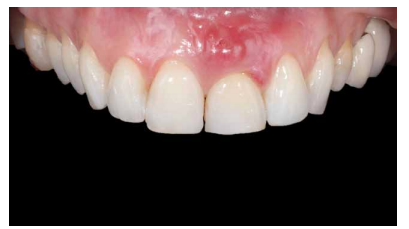

Evolución

Se llevó a cabo una primera revisión del procedimiento quirúrgico a los 7 días. Se observó una correcta cicatrización inicial de los tejidos blandos y ausencia de patología infecciosa o inflamatoria (Figura 18). A los 14 días se realizó una segunda revisión en la que se retiró la sutura (Figura 19). La revisión al mes de la cirugía mostró una correcta estabilidad inicial de los tejidos blandos y duros, así como la ausencia de signos relacionados con el fracaso del procedimiento (Figura 20).

A los 4 meses se evidenció una correcta estabilidad del IOI fruto de un correcto proceso de osteointegración. Respecto a los tejidos blandos, se podía observar una disminución del volumen de la papila interdental (Figura 21). Dada la ausencia de signos y síntomas y la correcta osteointegración del IOI, se realizó la modificación del perfil subcrítico con el fin mejorar la disposición del tejido blando gingival y favorecer la recuperación de dicha papila (Figuras 22 y 23).

A los 6 meses se puede observar una correcta disposición de los tejidos blandos, así como la estabilidad de estos en el tiempo debido al manejo de los mismos a través de la prótesis provisional (Figura 24). Se realizó además un control radiológico para conocer el estado de los tejidos duros (Figura 25).